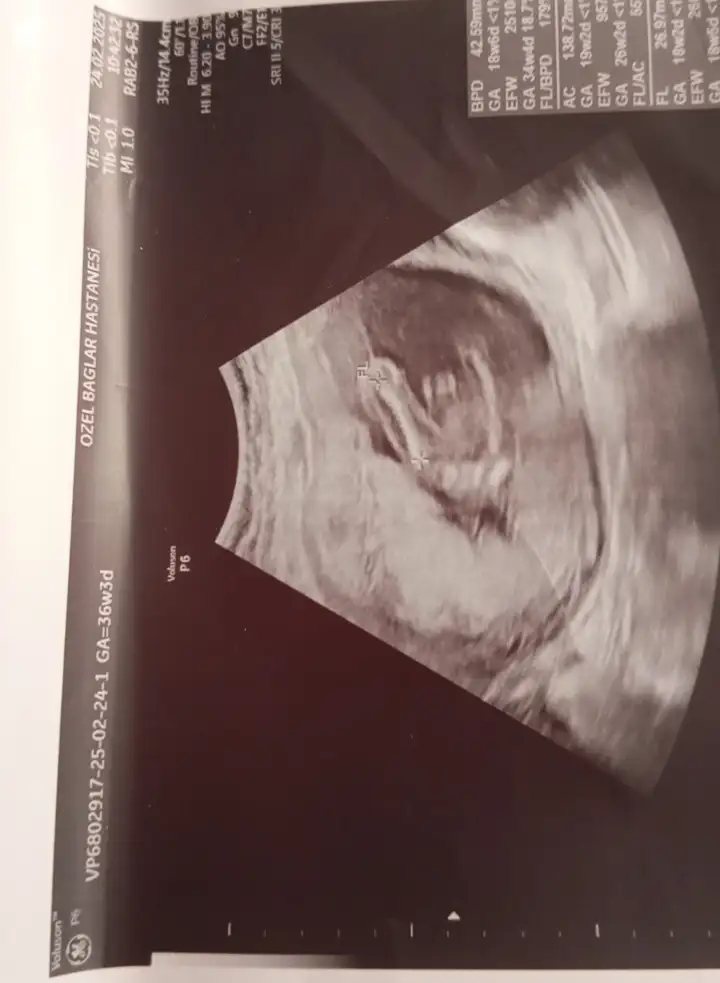

Bunlarada bakabilir misiniz

bacak arası görüntü anlamıyorum canımBunlarada bakabilir misiniz